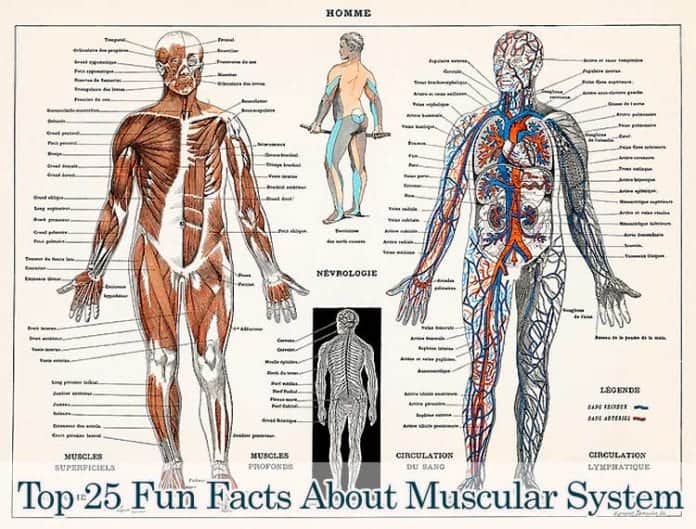

Fun Facts About The Muscular System: The human body comprises different systems interconnected with each other to serve the purpose of fulfilling all the essential functions of the body to sustain life. The muscular system is one such system that governs the functioning of all other organ systems.

The other organ systems are all innervated with muscles that help carry out daily functions. Muscles help the body move and are also responsible for creating facial expressions as we know them.

Apart from movements, the muscular system also works alongside the skeletal system to keep the body aligned and in the correct posture and also provides support.

Besides these, there are some interesting 25 fun facts about the muscular system.

At the high level, muscles of the human body are of three different types: skeletal, cardiac and smooth.

At the high level, muscles of the human body are of three different types: skeletal, cardiac and smooth.

- Skeletal muscles are attached to the bones and cartilage and help in movement and posture and support the human body.

- Cardiac muscles are found in the heart and are responsible for the heart’s pumping action.

- Smooth muscles are usually found lining the inside of different organs such as the liver, pancreas, and stomach and contain glands and cells that secrete different digestive juices. They are also present in other organ systems such as the respiratory system and the reproductive system.